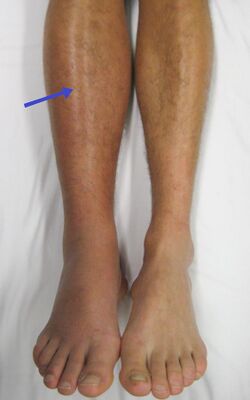

A deep vein thrombosis as seen in the right leg is a risk factor for PE

About 90% of emboli are from a deep vein thrombosis located above the knee termed a proximal DVT, which includes an iliofemoral DVT.[24] The rare venous thoracic outlet syndrome can also be a cause of DVTs, especially in young men without significant risk factors.[25] DVTs are at risk for dislodging and migrating to the lung circulation. The conditions are generally regarded as a continuum known as a venous thromboembolism (VTE).[citation needed]